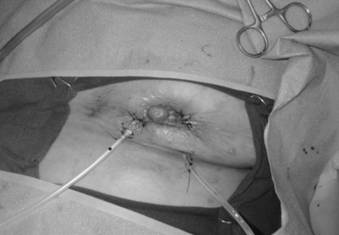

Figure 3

After debridement of the chronic breast abscess, a single wound vacuum-assisted closure (VAC) sponge was placed in the cavity; 2 VAC pads were used to apply negative pressure therapy through the 2 separate incisions.

J Cancer Image

Figure 4

The breast is shown after wound VAC sponge removal and delayed primary closure over drains. Note the volume loss secondary to the MBD skin and breast necrosis.

We subsequently admitted the patient to the hospital to perform an incision and drainage (I&D) of her left breast unresolving abscess cavity. We made an incision in the area of maximal fluctuance in the left breast in the periareolar region at 5 o'clock. To explore the borders of the cavity, we used a lacrimal probe; we noted that the cavity was connected to the sinus in the 8 o'clock position. The cavity measured approximately 8cm x 7cm x 2.5cm and contained necrotic tissue. Then, we made a separate incision over the sinus in the 8 o'clock position and completely excised the tract. Once we debrided the cavity, we placed a wound vacuum-assisted closure (VAC) device for negative pressure treatment with suction drainage (9, 10) through 2 separate incisions (Figures 1-4).